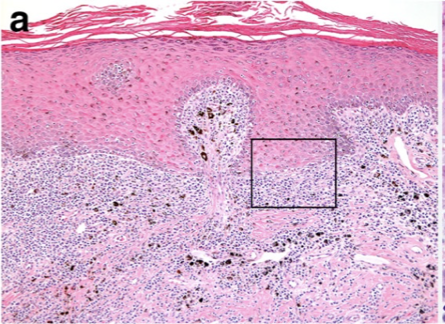

How does discoid lupus erythematous present histologically?

Sub-epidermal lymphoplasmacytic dermatitis (interface dermatitis)

Pigmentary incontinence (basal cell damage = melanin no longer held well)